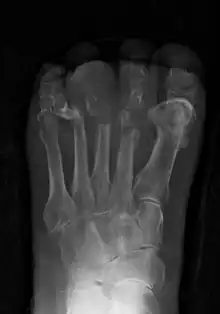

Radiographs and CT are the initial method of diagnosis, but are not sensitive and only moderately specific for the diagnosis. They can show the cortical destruction of advanced osteomyelitis, but can miss nascent or indolent diagnoses.[20]

Confirmation is most often by MRI. The presence of edema, diagnosed as increased signal on T2 sequences, is sensitive, but not specific, as edema can occur in reaction to adjacent cellulitis. Confirmation of bony marrow and cortical destruction by viewing the T1 sequences significantly increases specificity. The administration of intravenous gadolinium-based contrast enhances specificity further. In certain situations, such as severe Charcot arthropathy, diagnosis with MRI is still difficult.[20] Similarly, it is limited in distinguishing bone infarcts from osteomyelitis in sickle cell anemia.[21]

Diagnosis of osteomyelitis is often based on radiologic results showing a lytic center with a ring of sclerosis.[10] Culture of material taken from a bone biopsy is needed to identify the specific pathogen;[23] alternative sampling methods such as needle puncture or surface swabs are easier to perform, but do not produce reliable results.[24][25]